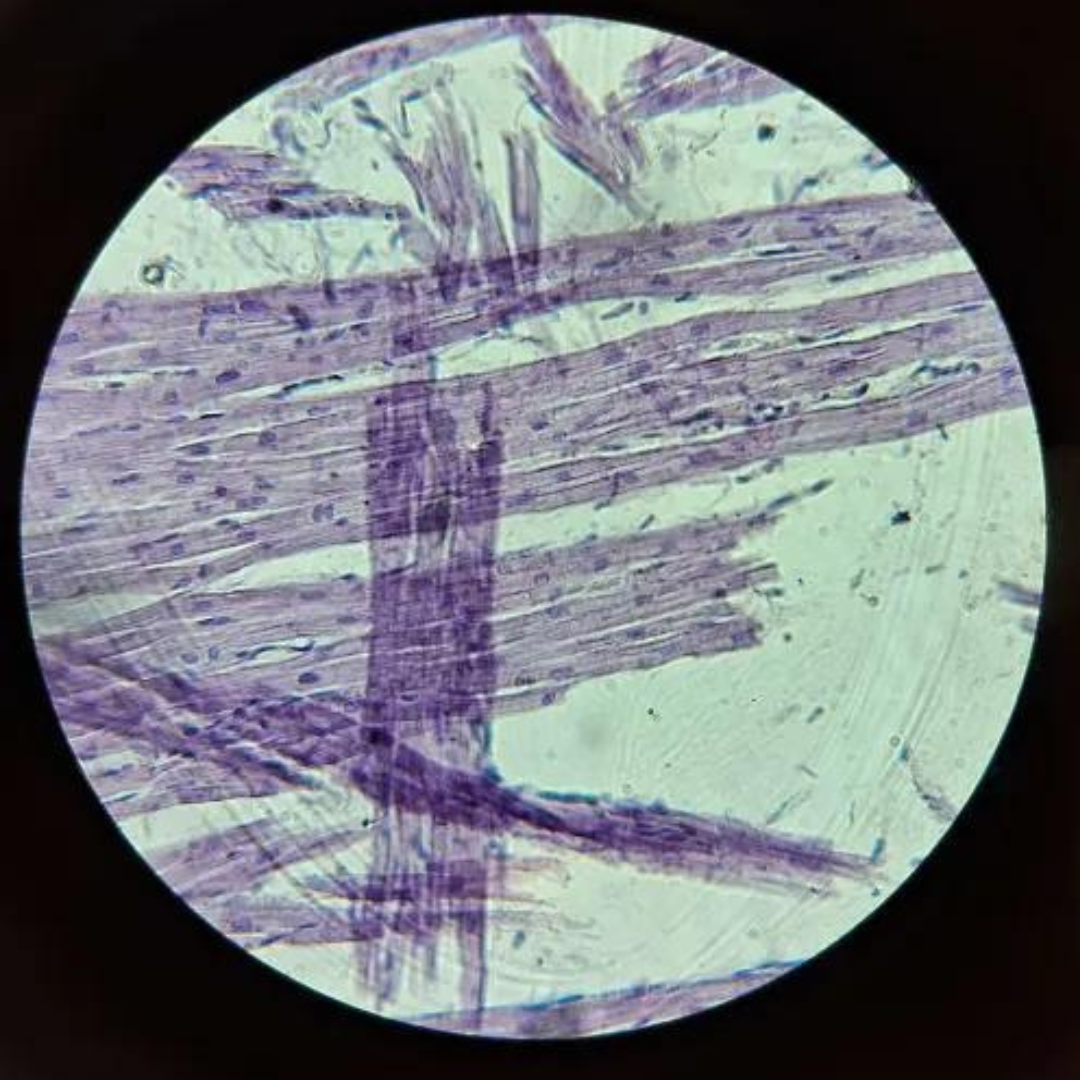

Reticular Connective Tissue (Lymph Node)